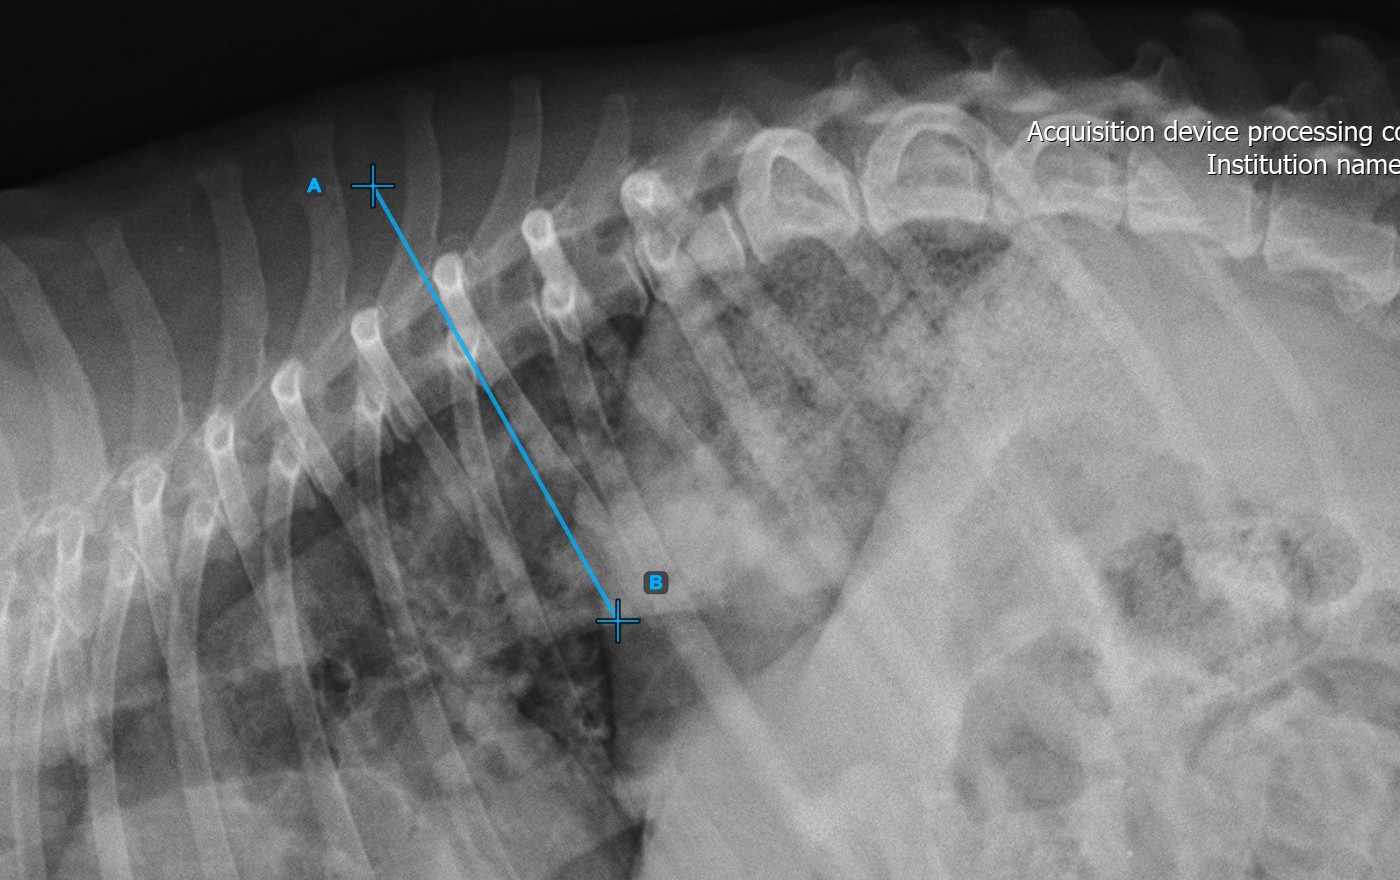

The image below represents a typical placement of the first vertebral line.

../../_images/image373.jpg

Start the measurement by marking the first vertebral line on the spine.

Identify the vertebral endplate at the initial point of the largest spinal curve deformity. Place the start and end point of the first vertebral line precisely along the identified endplate. Adjust each point on the scene to better align the line with the endplate if needed.